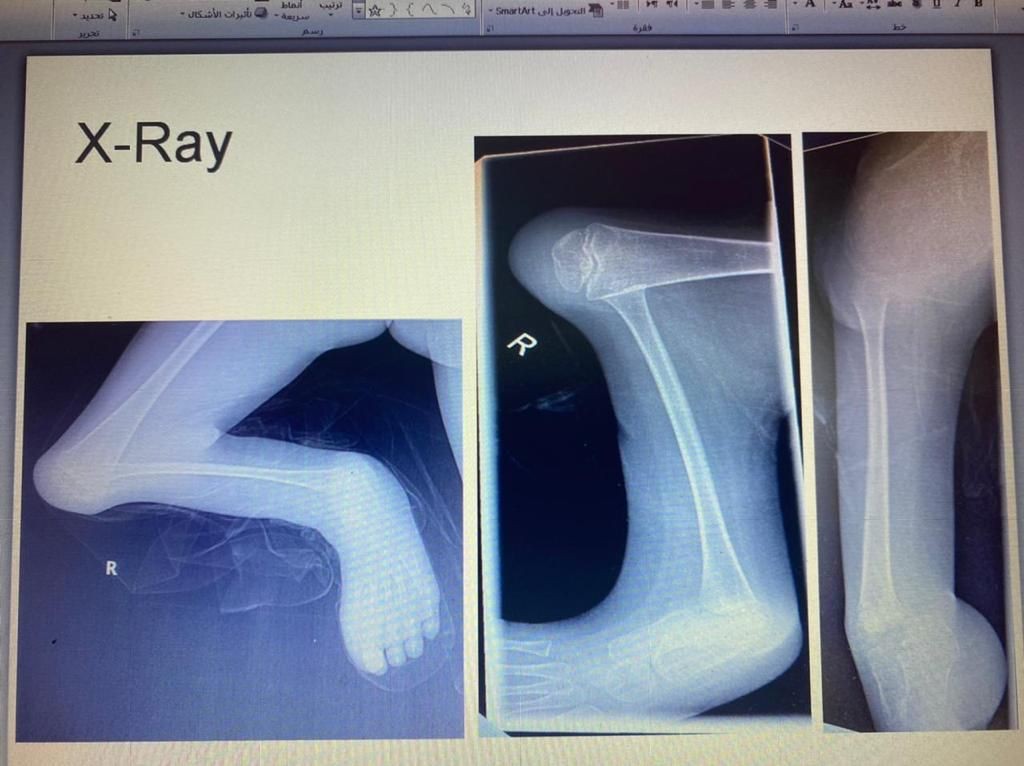

نجح الفريق الطبي في قسم جراحة العظام بمستشفى الملك فهد العام بجدة بقيادة الدكتور عبدالهادي العمودي من إجراء عملية جراحية لطفل بعمر 8 اعوام في ساقه اليمنى تحديداً بعظمة القصبة الرئيسية وإيجاد عظمة شظية ثانوية بالساق اليمنى.

وبعد عمل الفحوصات الطبية اتضح أن الطفل يعاني من تشوه خلقي لفقدانه عظمة القصبة بالساق اليمنى وتم  قيام الفريق الطبي بإجراء عملية جراحية تكميلية لعظمة الشظية بالساق لتعويض القصر في العظمة، وتمكن الأطباء بعملية توفير عظمة الشظية من عظمة الفخذ باستخدام جهاز الاليزروف وتم تعديل القدم تحت عظمة القصبة بالشظية وإدراج القدم تحت عظمة الشظية.

ثم بفضل الجهود المتواصله من قبل الفريق الطبي المتمكن تكللت العملية الجراحيه بنجاح ولله الحمد وعودة الساق إلى شكلها الطبيعي بعد أن كانت العظمة مفقودة.

كما وتم الانتهاء من الرعاية الطبية اللازمة ما بعد العملية وعودة الطفل لممارسة حياته شبه الطبيعية ليقوم بالتحرك والمشي عليها بعد وضع طرف صناعي سفلي لتعويض فارق الطول، واستكمال للتدخل الطبي تم وضع خطة علاجية لإجراء عملية تطويل الساق خلال الأسابيع القادمة بإذن الله.